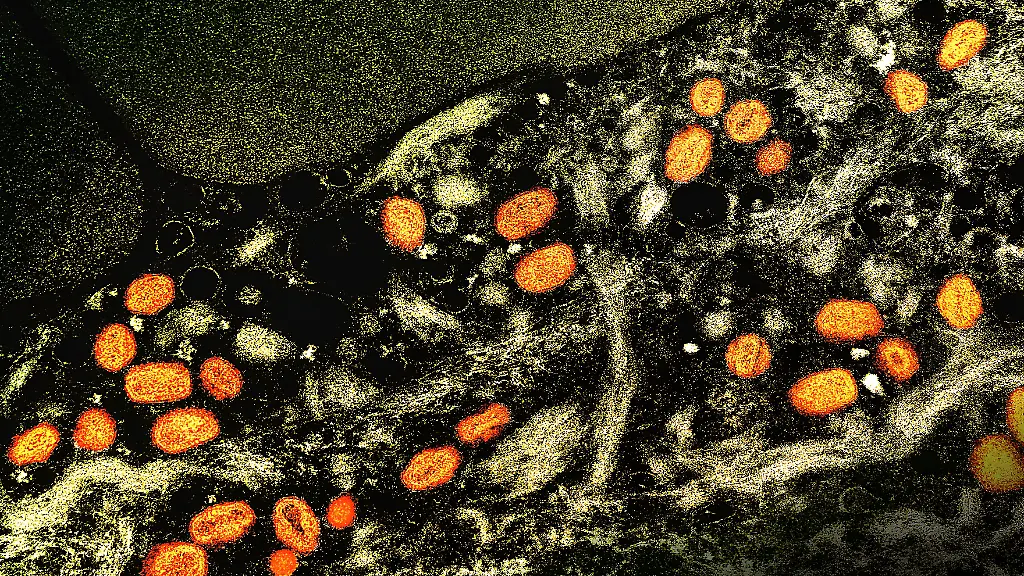

Infektionen in GroßbritannienNeue Mpox-Variante erstmals in Europa übertragen

Eine neue Mpox-Variante breitet sich derzeit in Afrika aus. Sie soll ansteckender und gefährlicher sein als ihre Vorgängerin. Nun infizieren sich erstmals Menschen in Europa - und zwar in Großbritannien.

Erstmals haben sich Menschen in Europa mit der neuen Variante des Mpox-Virus angesteckt. Das teilte die Weltgesundheitsorganisation (WHO) mit. In Großbritannien infizierten sich demnach zwei Menschen mit der sogenannten Klade Ib. Sie lebten im gleichen Haushalt wie eine Person, die kurz nach einer Reise in mehrere afrikanische Länder positiv getestet worden sei.

Es handle sich um die ersten lokal übertragenen Mpox-Klade-Ib-Fälle in der europäischen Region der WHO und auch um die ersten außerhalb Afrikas, seit die WHO im August einen internationalen Gesundheitsnotstand ausgerufen habe. Das ist die höchste Alarmstufe, die Behörden in aller Welt zu erhöhter Aufmerksamkeit bringen soll.